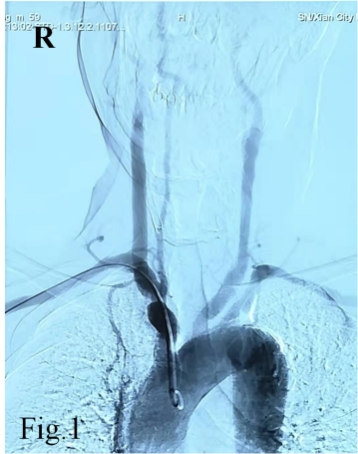

55岁的白先生因急性脑梗死入住我院神经内科,双侧颈部血管、锁骨上窝均可闻及血管杂音,为详细评估脑血管情况,拟行全脑血管造影检查。常规的脑血管造影检查首选右侧股动脉穿刺入路完成造影,但是该患者存在明确的右下肢间歇性跛行病史,双侧股动脉搏动触摸不到。下肢动脉超声提示双侧股动脉中度狭窄,股动脉、腘动脉等下肢血管动脉粥样硬化斑块形成。仔细评估后,考虑无法从股动脉穿刺进行造影检查。经神经介入医生周密准备,拟进行经右侧桡动脉穿刺完成脑血管造影及下肢血管造影检查。

经过导丝引导下,谨慎地将造影导管置于主动脉弓,造影显示Ⅱ型主动脉弓,介入医生顿感压力倍增。常规路径下(股动脉置管),Ⅱ型主动脉弓要比Ⅰ型主动脉弓操作难度复杂的多,颈部血管从主动脉弓发出角度、走形、迂曲度及造影导管在主动脉弓如何塑形、塑形成功率等等都会制约操作时间、顺畅性,稍有不慎可能导致主动脉弓斑块脱落、主动脉动脉夹层等情况发生。增加了在经桡动脉在Ⅱ型主动脉弓上超选造影的难度。经介入医生耐心、细致操作下,反复尝试降主动脉造影导管成型,逐步“逆行”完成全脑血管造影及下肢动脉造影。